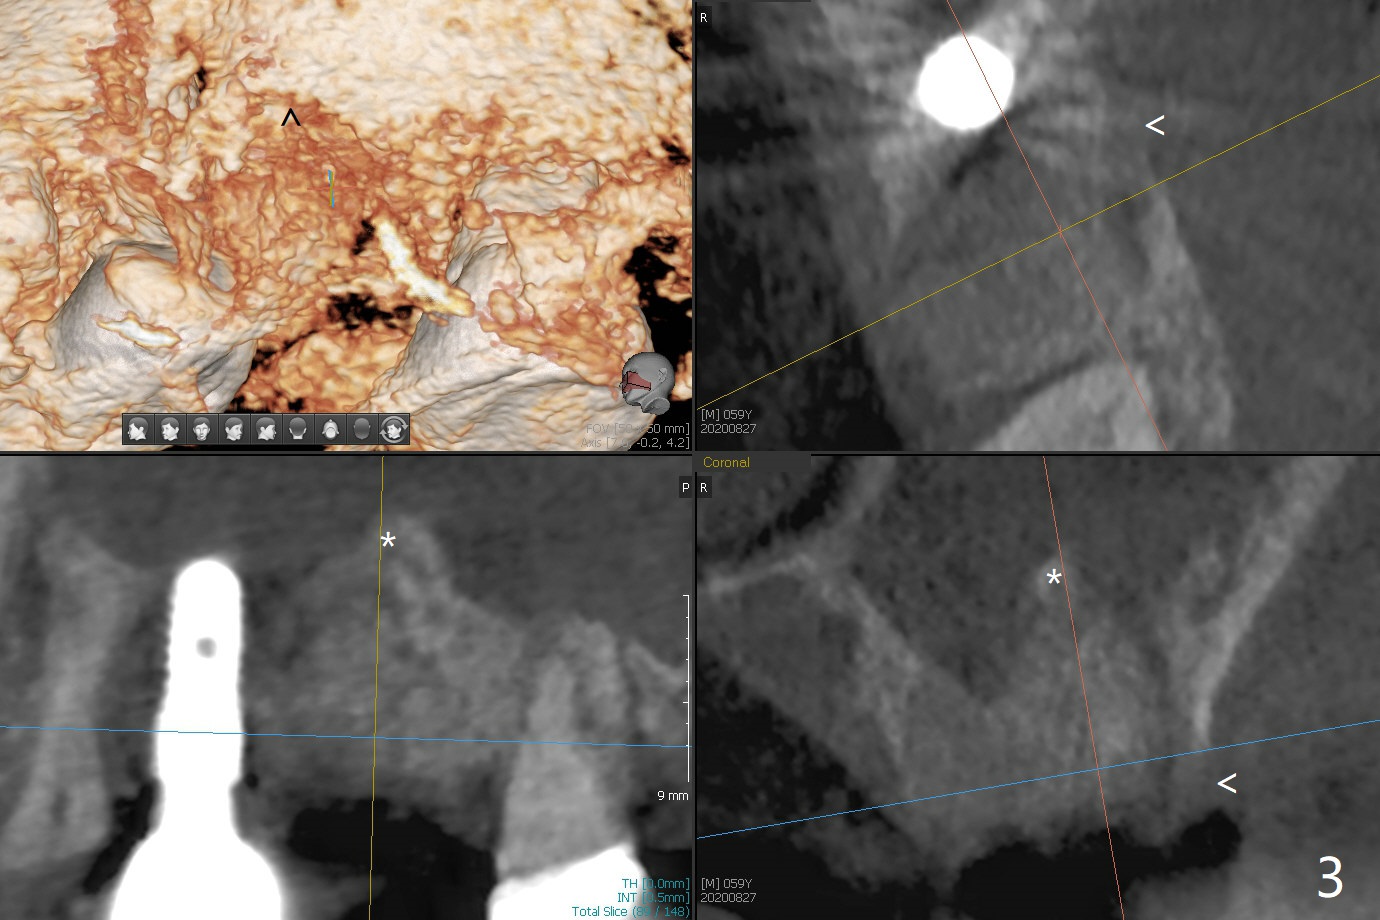

左上六拔除后,近中颊侧窝尤其大,与上颌窦相通(图一 *),而中隔比较尖,截除后还显得窄(图一,二:S),不太适合即刻种植。放置一块PRF膜于近中颊侧窝修补上颌窦,然后放置粘性骨块,好像有上颌窦提升迹象(图三:*(箭头:近中颊侧骨板缺失)),用骨粉填满其余牙槽窝(图四),覆盖另外一块PRF膜以及Cytoplast(不可吸收膜),用PTFE缝线(也不可吸收,与膜是同一个材料,非常柔软,好打结)缝合(图五)。最后使用牙周敷料。后者术后八九天脱落,病人术后十二天复诊,不可吸收膜腭侧有些外翻(图六箭头),伤口愈合尚可,没有骨粉丢失迹象,反复交代口腔卫生。再过三周撤除不可吸收膜。其实三周后膜自己脱落,病人回来撤去剩余缝线(图七),新鲜肉芽组织形成。术后5个月牙槽嵴和角化龈宽,骨高度尚可(图八),密度差些(图九,750单位),植体应该是4.5x8.5 或者 10 毫米,少量上颌窦提升。